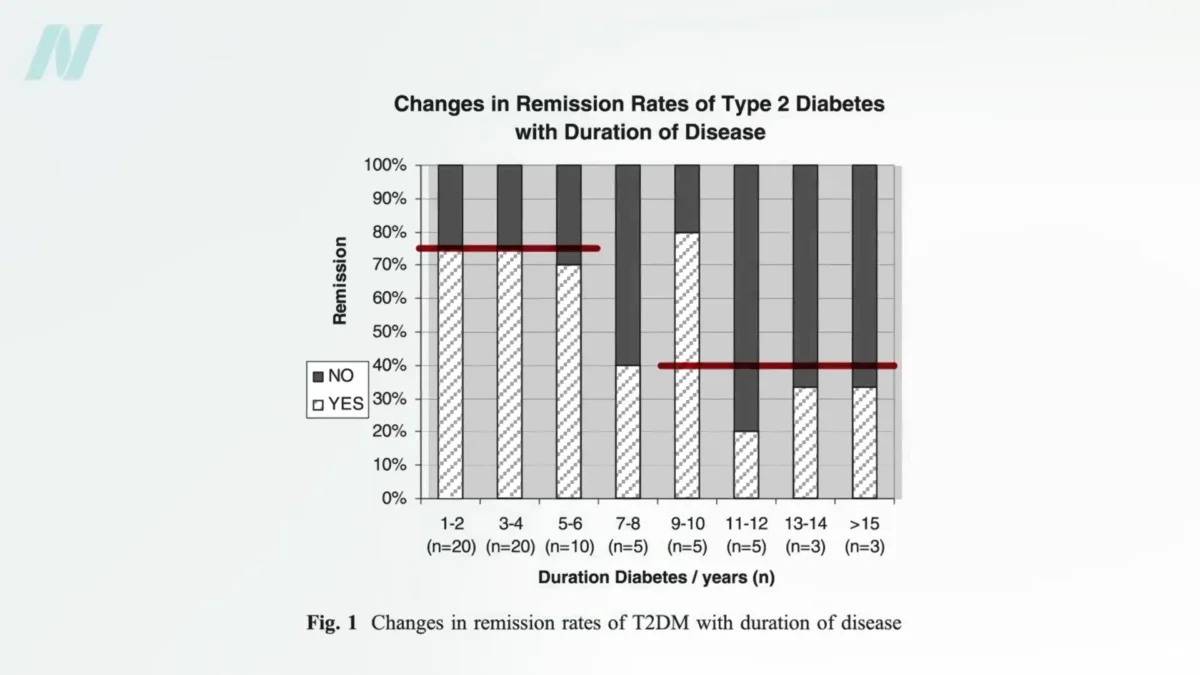

Promising Short-Term Effects Observed in Recent Studies, But Long-Term Efficacy Remains an Open Question

A comprehensive analysis of recent scientific studies has illuminated a series of encouraging short-term outcomes associated with a particular area of research, though significant questions persist regarding its long-term efficacy…